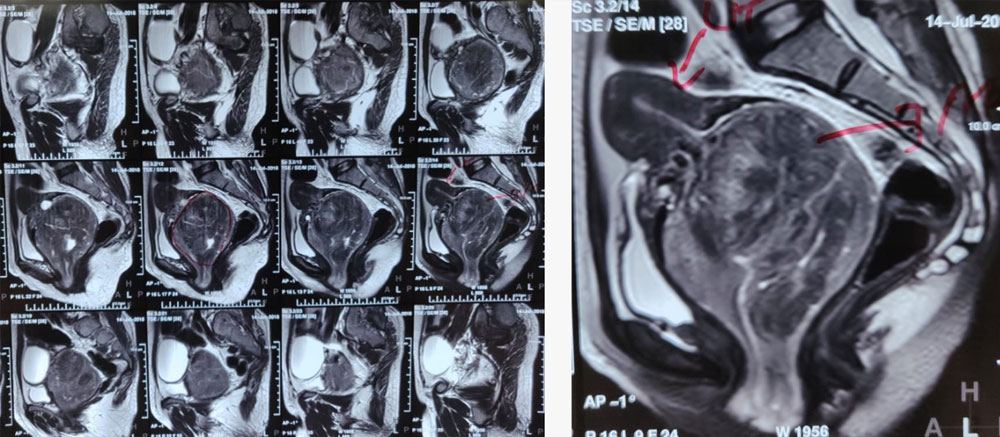

Uterine fibroid embolization is a minimally invasive treatment for symptomatic uterine fibroids. It is a safe and effective alternative to hysterectomy for the majority of women.

Uterine fibroid embolization is performed by interventional radiologists, who are physicians specially trained in minimally invasive procedures. A small catheter is inserted into the femoral artery in the groin and threaded through the blood vessels to the uterus. Once the catheter is in place, the interventional radiologist uses x-ray guidance to carefully insert a small coil or particles into the blood vessels that supply the fibroid. These particles block the blood flow to the fibroid, causing it to shrink.